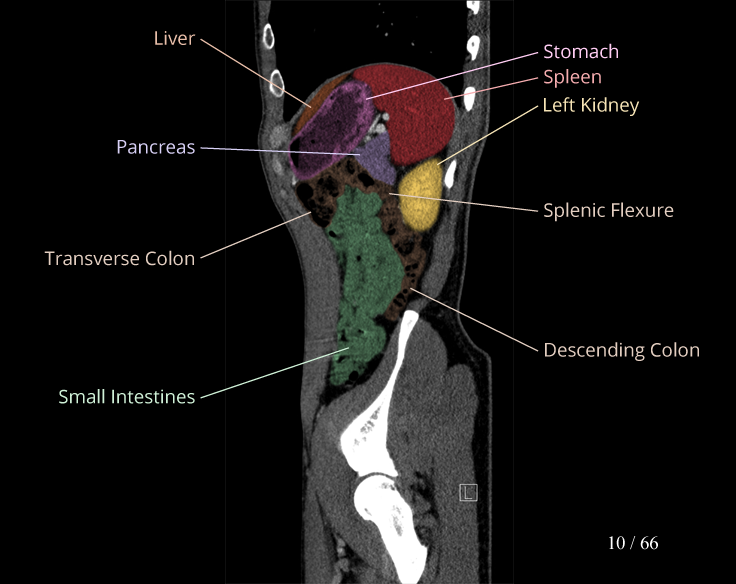

Body

Covers abdominal CT anatomy.